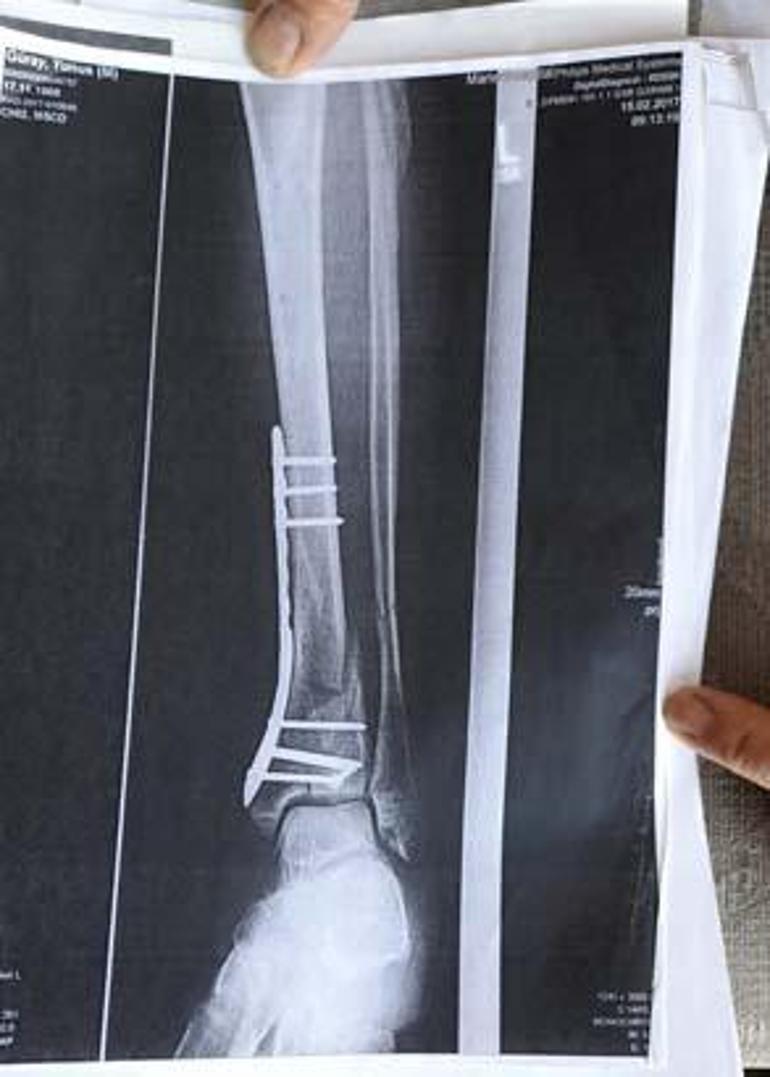

‘DEMİR VAR AYAĞIMDA, SAKAT BIRAKTILAR'

Olay yeriyle ilgili fotoğraf ve görüntüleri mahkemeye sunduklarını kaydeden Güray, "Ömrümü yediler, demir var ayağımda, sakat bıraktılar. Ayağı keseceklerdi neredeyse. Şu an kalıcı sakatlık var. 1 sene kendime gelemedim, 2 haftada bir ameliyata giriyordum. Almanya'da 3 ay hastanede kaldım ve ayağımda yüzde 3'lük engel oluştu" diye konuştu.